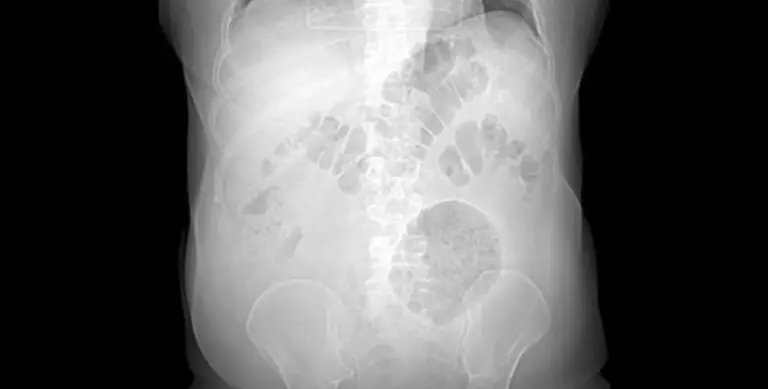

Legenda: Roberto Luiz foi diagnosticado com leptospirose e se recuperou após estado grave no hospital

A questão é que a leptospirose de Roberto evoluiu para Síndrome de Weil, manifestação mais grave da doença, demonstrando a pela alaranjada, hemorragia e insuficiência renal.